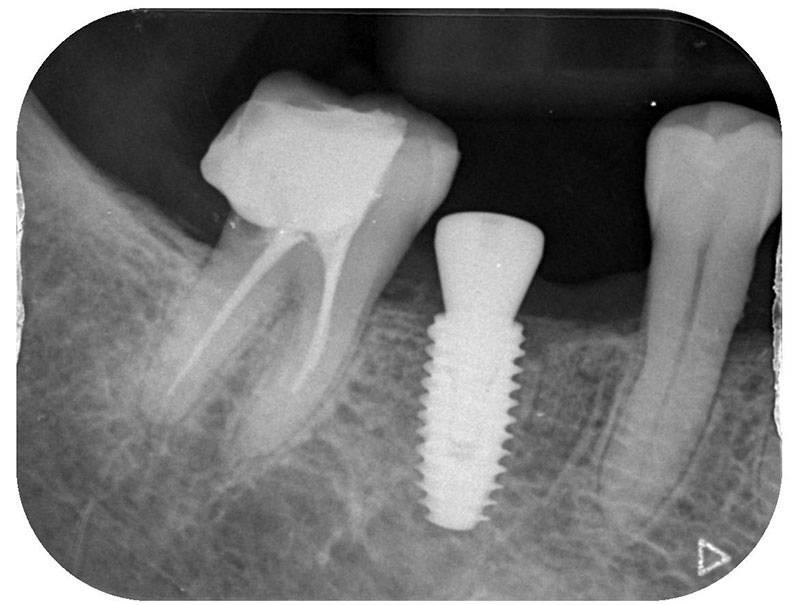

インプラント埋入手術

インプラントの埋入に関しては1回法で行いました。抜歯した部位の骨はしっかりと治癒していました。インプラント埋入後はヒーリングキャップと言ってインプラント周囲の歯茎の形態を整えるためのキャップを装着しました。手術時は特に大きな問題はなく無事に手術が終了しました。

インプラントの埋入に関しては1回法で行いました。抜歯した部位の骨はしっかりと治癒していました。インプラント埋入後はヒーリングキャップを装着しました。手術時は特に大きな問題はなく無事に手術が終了しました。インプラントの露出を避けるためにも骨幅が少しでも広いところに埋入するために理想的な位置よりは少し後ろになっています。